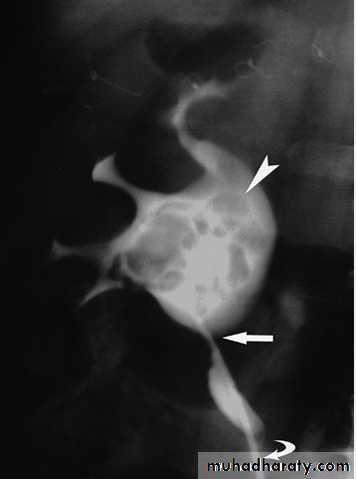

Radiograph from an excretory urogram demonstrates mild dilation of the right ureter associated with a simple ureterocele (u) that protrudes into the lumen of the bladder (B). The radiolucent wall of the ureterocele (arrowhead) is outlined by contrast within the ureterocele and contrast within the bladder lumen. The wall of the ureterocele is made up of the wall of the ureter and the bladder mucosa.

Bilateral ureteroceles. dilatation of the distal ureter as it enters through the bladder wall. This produces a typical “cobra head” deformity (arrows.

Benign Prostatic Hypertrophy. A radiograph from an excretory urogram shows marked uplifting of the bladder base because of massive enlargement of the prostate (P). The trigone (open arrow) and ureteral orifices (black arrows) are markedly elevated, resulting in a J-shaped appearance to the distal ureters (u). The bladder wall is thickened (between black arrowheads), and the bladder (B) mucosal pattern is prominent.